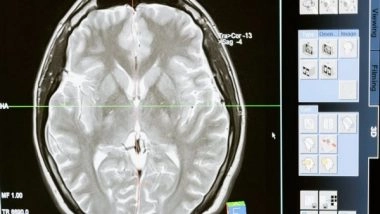

The current research, led by Professor Dominique de Quervain and Professor Andreas Papassotiropoulos at the University of Basel, investigates the role of the cerebellum in storing emotional experiences. In a large-scale study, the researchers showed 1,418 participants emotional and neutral images and recorded the subjects' brain activity using magnetic resonance imaging.

In a memory test conducted later, the positive and negative images were remembered by the participants much better than the neutral images. The improved storage of emotional images was linked with an increase in brain activity in the areas of the cerebrum already known to play a part. However, the team also identified increased activity in the cerebellum.